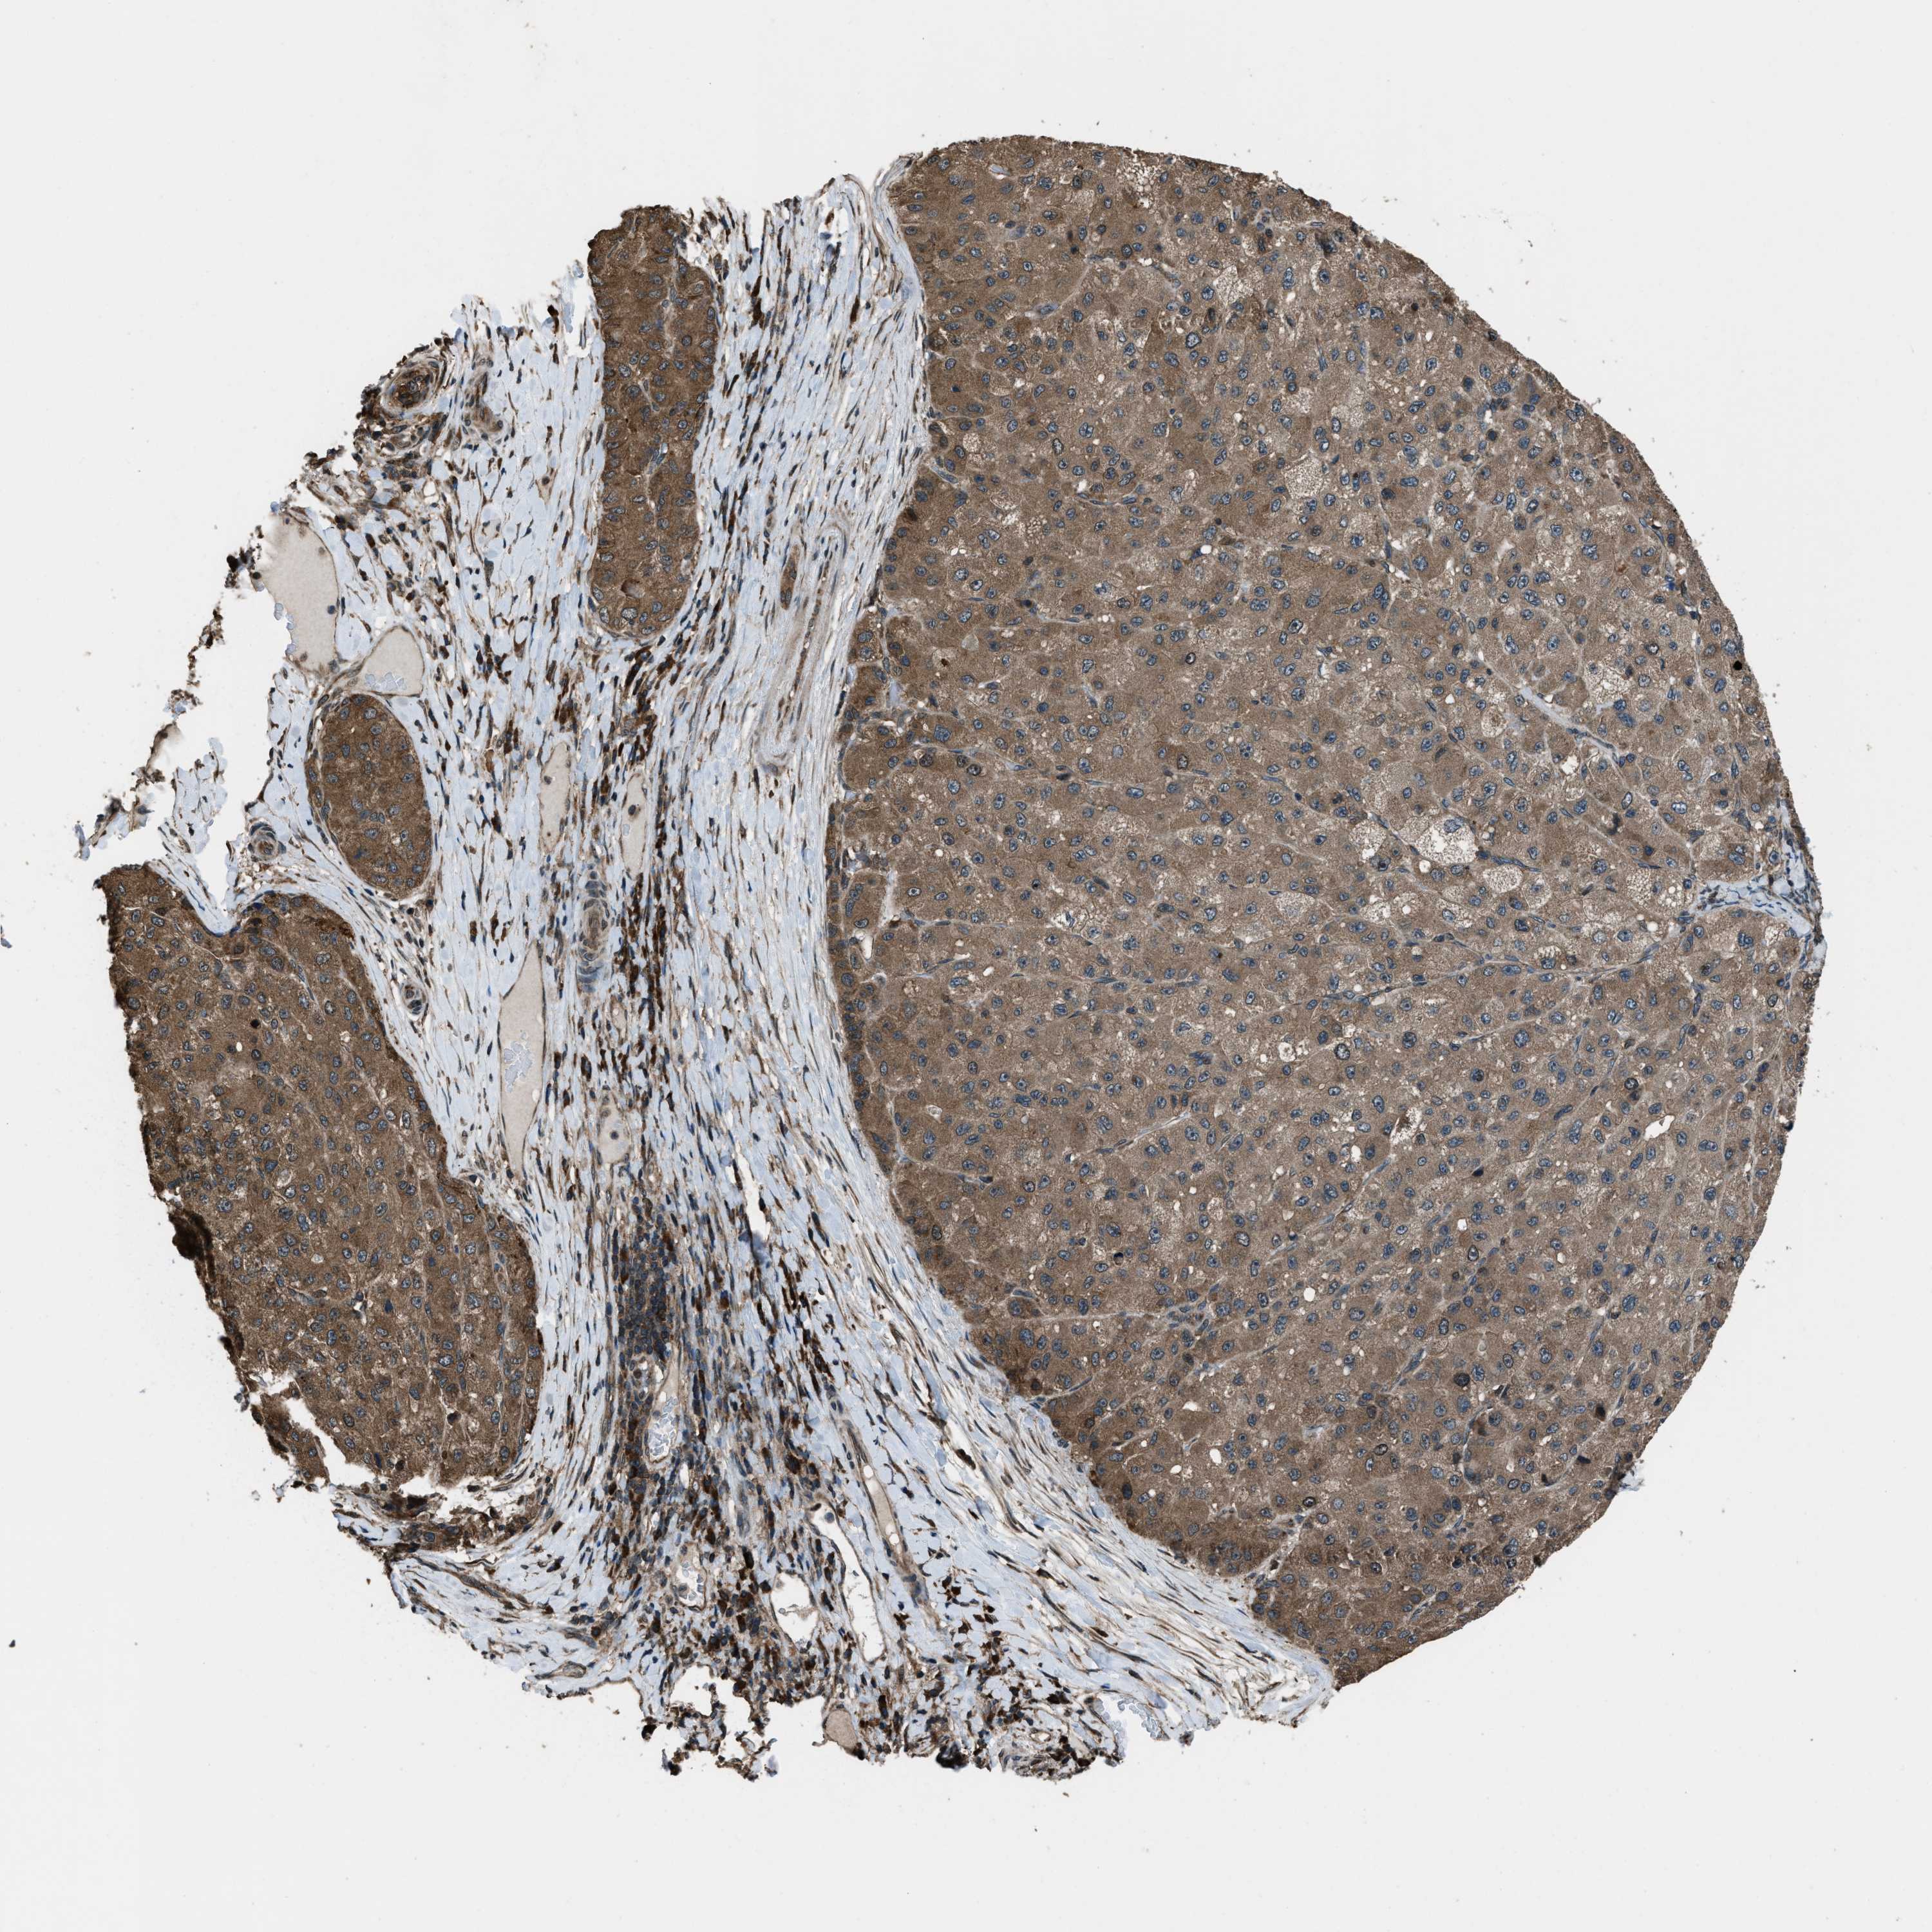

LIVER CANCER - Protein expressioni

A mouse-over function shows sample information and annotation data. Click on an image to view it in a full screen mode. Samples can be filtered based on level of antibody staining by selecting one or several of the following categories: high, medium, low and not detected. The assay and annotation is described here.

Note that samples used for immunohistochemistry by the Human Protein Atlas do not correspond to samples in the TCGA dataset.

Antibody stainingi

Antibody staining in the annotated cell types in the current human tissue is reported as not detected, low, medium, or high, based on conventional immunohistochemistry profiling in selected tissues. This score is based on the combination of the staining intensity and fraction of stained cells.

Each image is clickable and will lead to virtual microscopy that enables deeper exploration of all samples and also displays staining intensity scores, fraction scores and subcellular localization as well as patient and tissue information for each sample.

Antibody HPA019356

Antibody HPA029461

Staining

High

Medium

Low

Not detected

Intensity

Strong

Moderate

Weak

Negative

Quantity

>75%

75%-25%

<25%

None

Location

Nuclear

Cytoplasmic/membranous

Cytoplasmic/membranous,nuclear

Cholangiocarcinoma

Carcinoma, Hepatocellular, NOS